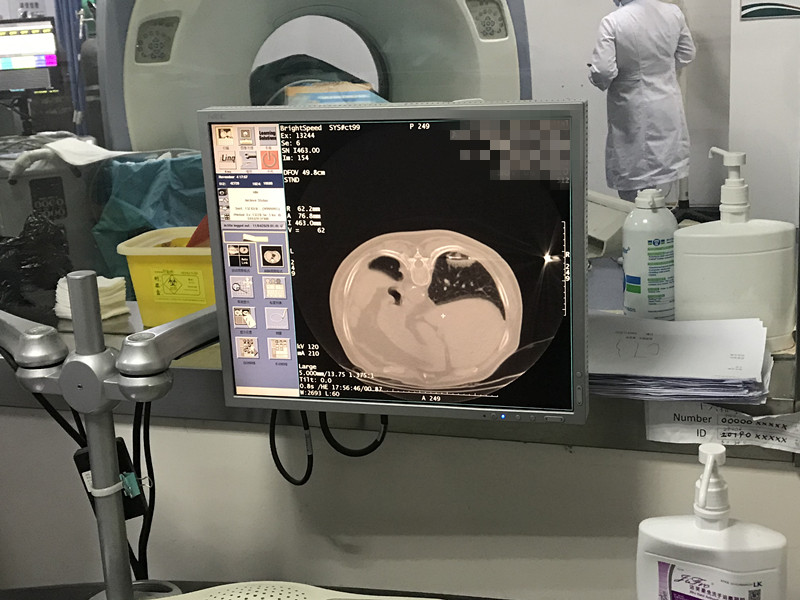

79岁患者肺部氩氦刀冷冻消融

发布人:美国氩氦刀技术官方网站    发布时间:2020/11/16 15:15:03